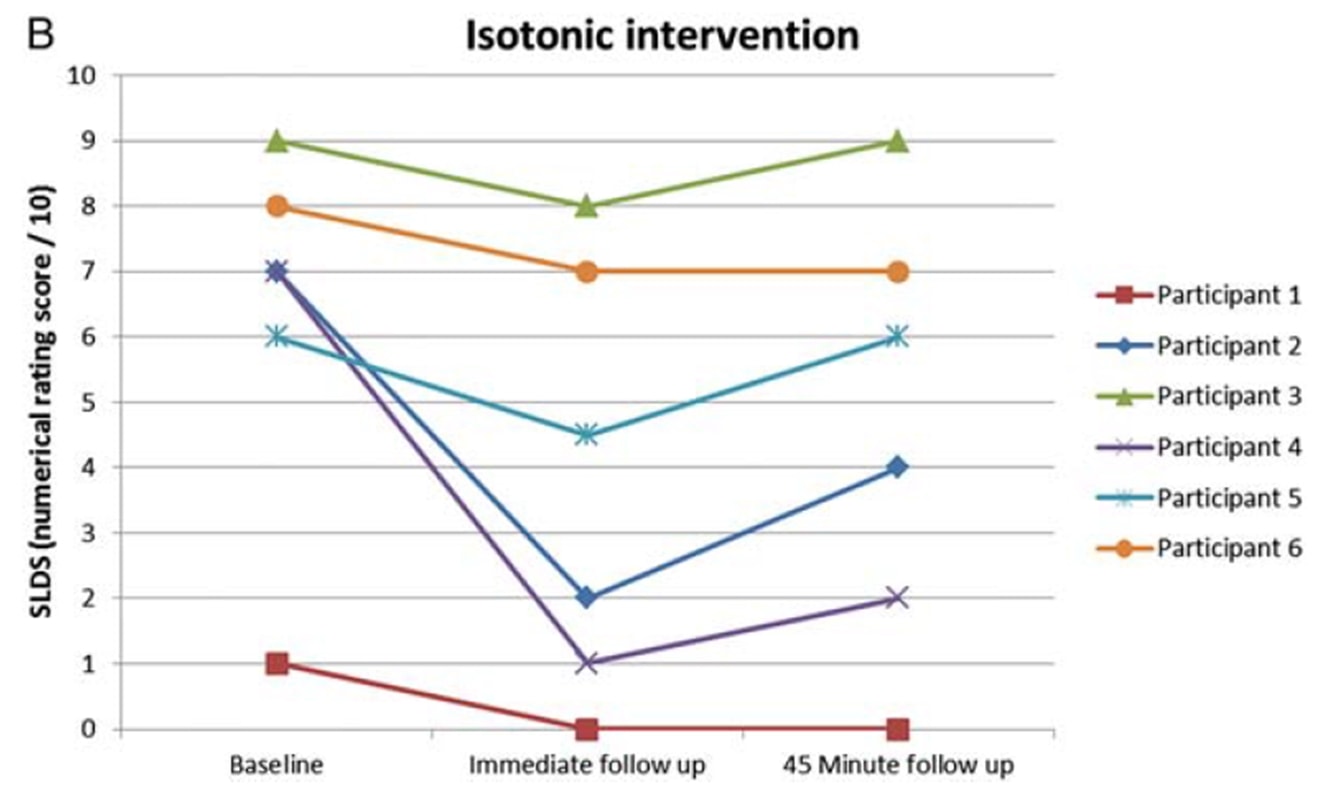

里奥等人 (2015) 当他们对 6 名患有髌骨肌腱病的排球运动员进行交叉试验时,掀起了一股风潮。 他们的研究结果令人吃惊,所有运动员的疼痛都立即减轻,从 NRS 平均 7/10 减轻到 0,6 名运动员中只有一人在等长收缩后至少 45 分钟内仍感到 1- 的疼痛。 他们采用的方案是在伸腿机上进行 5 组 45 秒的收缩,用力达到最大自主用力的 70%。 他们还发现,等距运动能够减少大脑皮层的抑制作用,使力量增加 19%。 他们将等长干预与等张干预进行了比较,结果等长干预组无法达到等张干预组的效果:

同一作者还在两年后对跳跃运动员进行了赛季内跟踪研究(Rio et al. 2017)中,他们对等长程序和等张程序进行了比较。 在这项研究中,两组的结果差异较大,等长组的即时疼痛减轻程度更高: